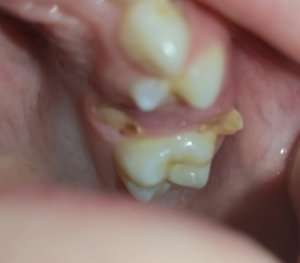

Мне 26 лет, молочные зубы менялись поздно. По личным причинам, когда стал резаться коренной зуб (клык), я не стала вырывать молочный, который был крепким и здоровым. Так на протяжении нескольких лет (очень медленно) прорезался коренной клык и наконец вырос, но на нёбе. Так я ходила с двумя зубками. Никаких неудобств не ощущала. Совсем недавно молочный зуб резко (в течение трёх дней) потемнел.